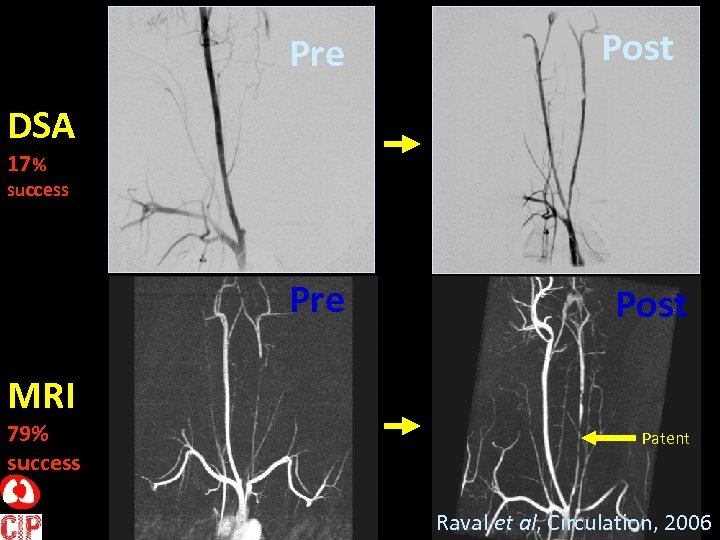

Peripheral Chronic Total Occlusion RCA LCA RSCAD SVC Carotid Trunk T Raval et al, Circulation, 2006

Pre Post DSA 17 % success Pre Post MRI 79% success Patent Raval et al, Circulation, 2006